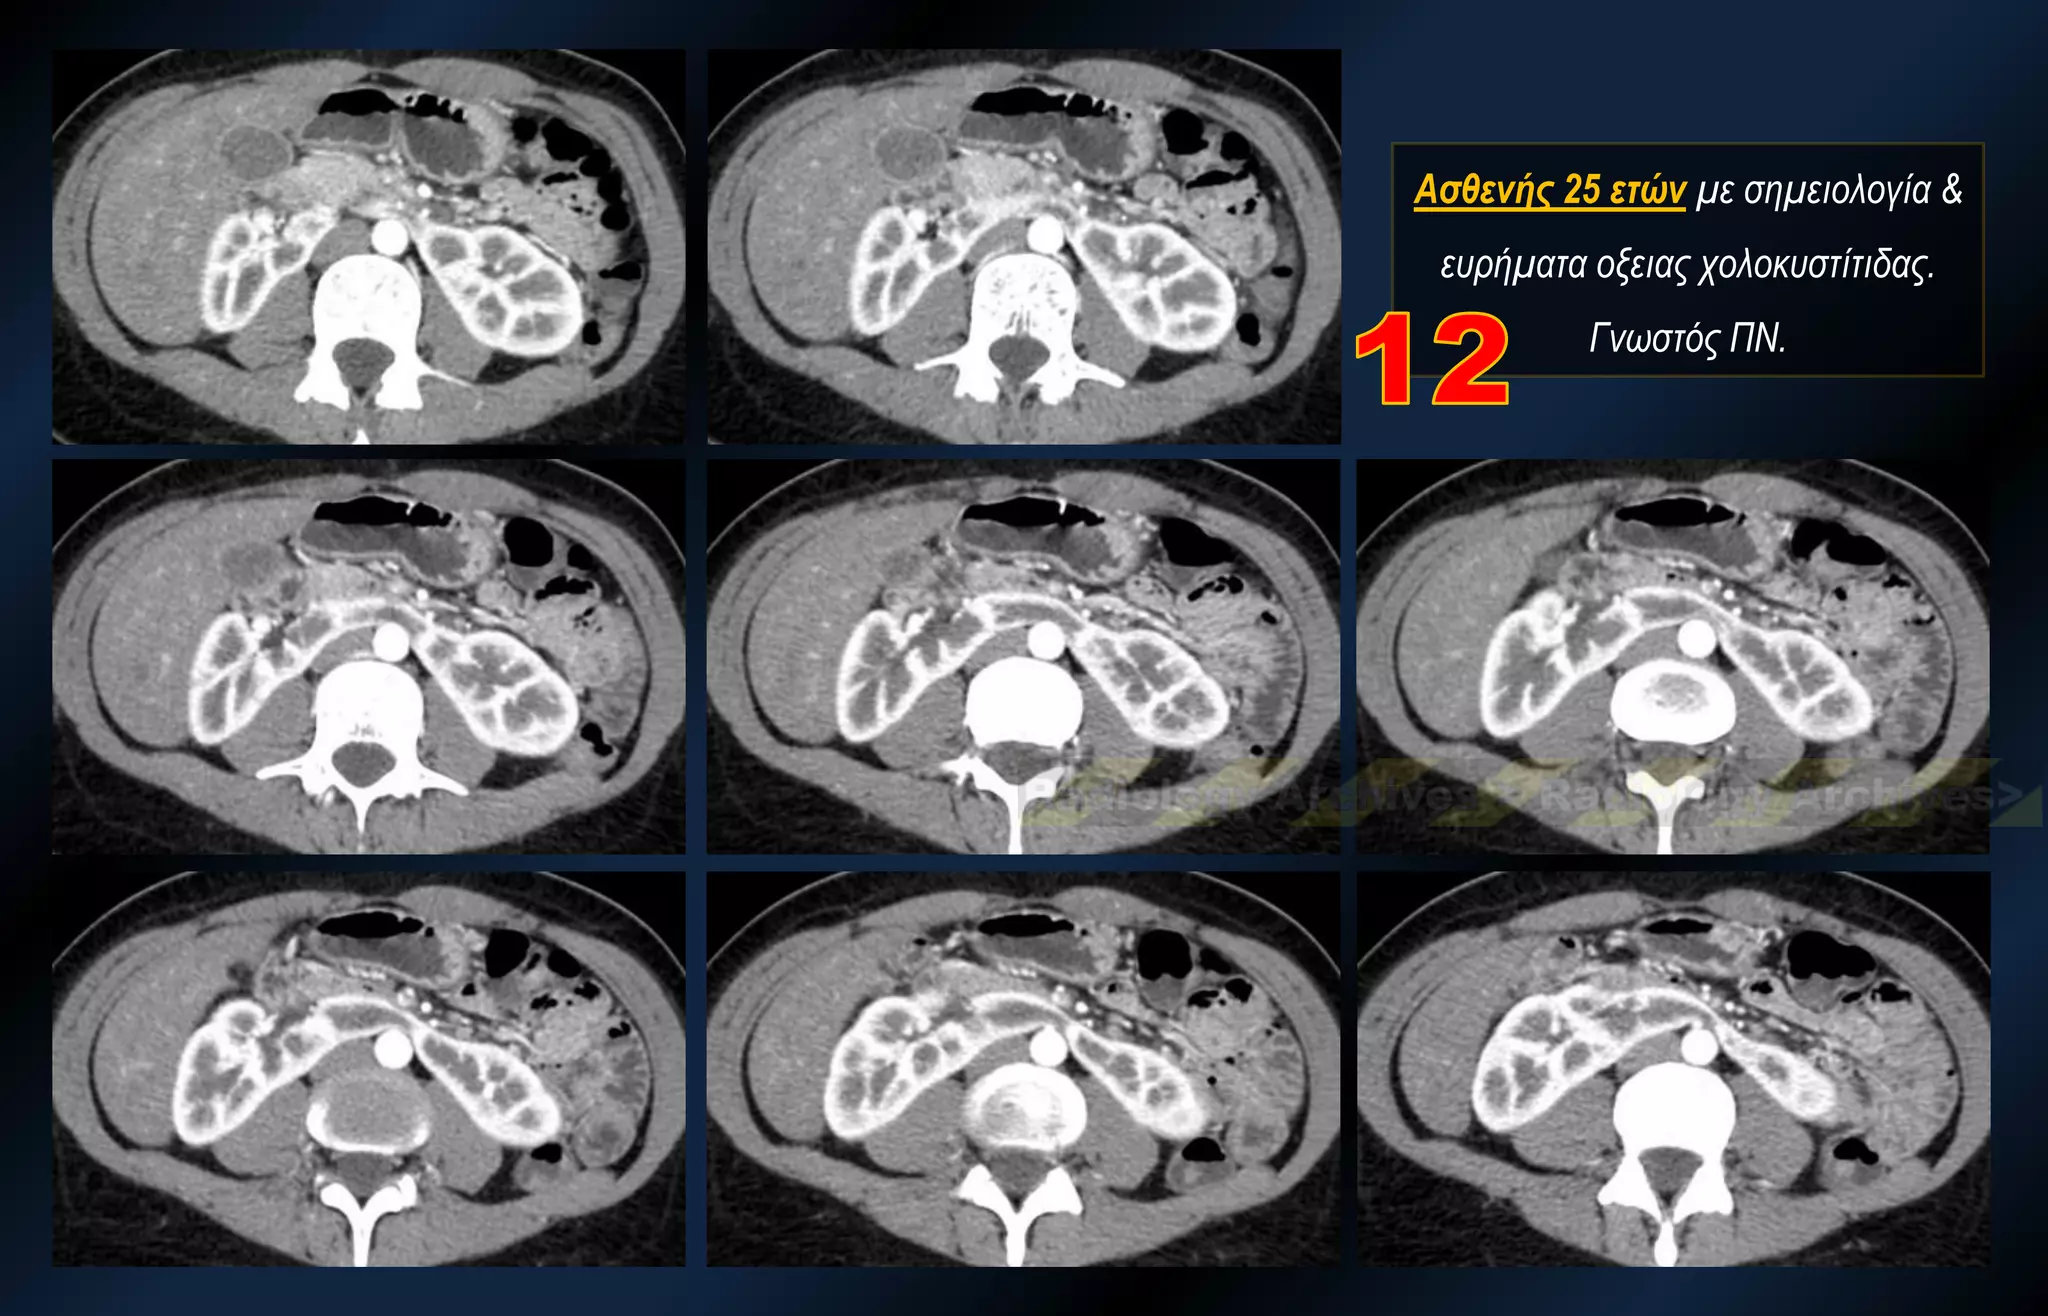

Ασθενής 25 ετών με σημειολογία & ευρήματα οξειας χολοκυστίτιδας. Γνωστός ΠΝ.

Ασθενής 25 ετώνμε σημειολογία & ευρήματα οξειας χολοκυστίτιδας. Γνωστός ΠΝ.